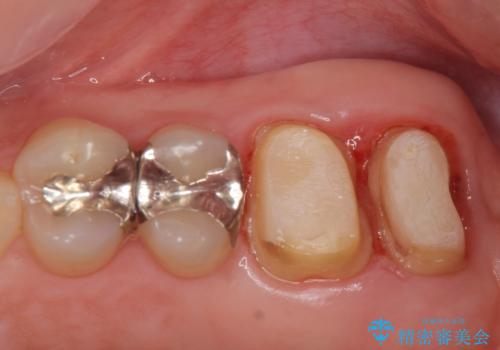

- 銀歯をやりかえたいが他院で抜歯と言われセカンドオピニオンで来院。適合の悪い被せ物が入っており、まずは古い材料、虫歯をとり保存可能か確かめる必要があり、拡大鏡下で全て取り除いたら歯質が歯茎の中まで虫歯がありました。このまま無理やり型取りをして被せ物を作っても不適合な被せ物が入る可能性が高いため歯茎を切り取る手術(ディスタルウェッジ)を行いました。そして再根管治療を行いゴールドの被せ物で治療を行いました。